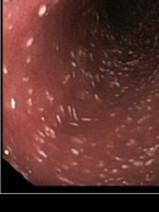

• Soirée - Diarrhées chroniques du chat : l'embarras du chat, le tracas du praticien, un défis diagnostic et thérapeutique au quotidien !

Vous souhaitez approfondir vos connaissances sur les dernières avancées en gastroentérologie féline ? Participez à notre formation "Actualités en gastroentérologie féline" et découvrez les innovations, les nouvelles recherches et les meilleures pratiques du domaine.

Cette formation vous permettra de mieux diagn...